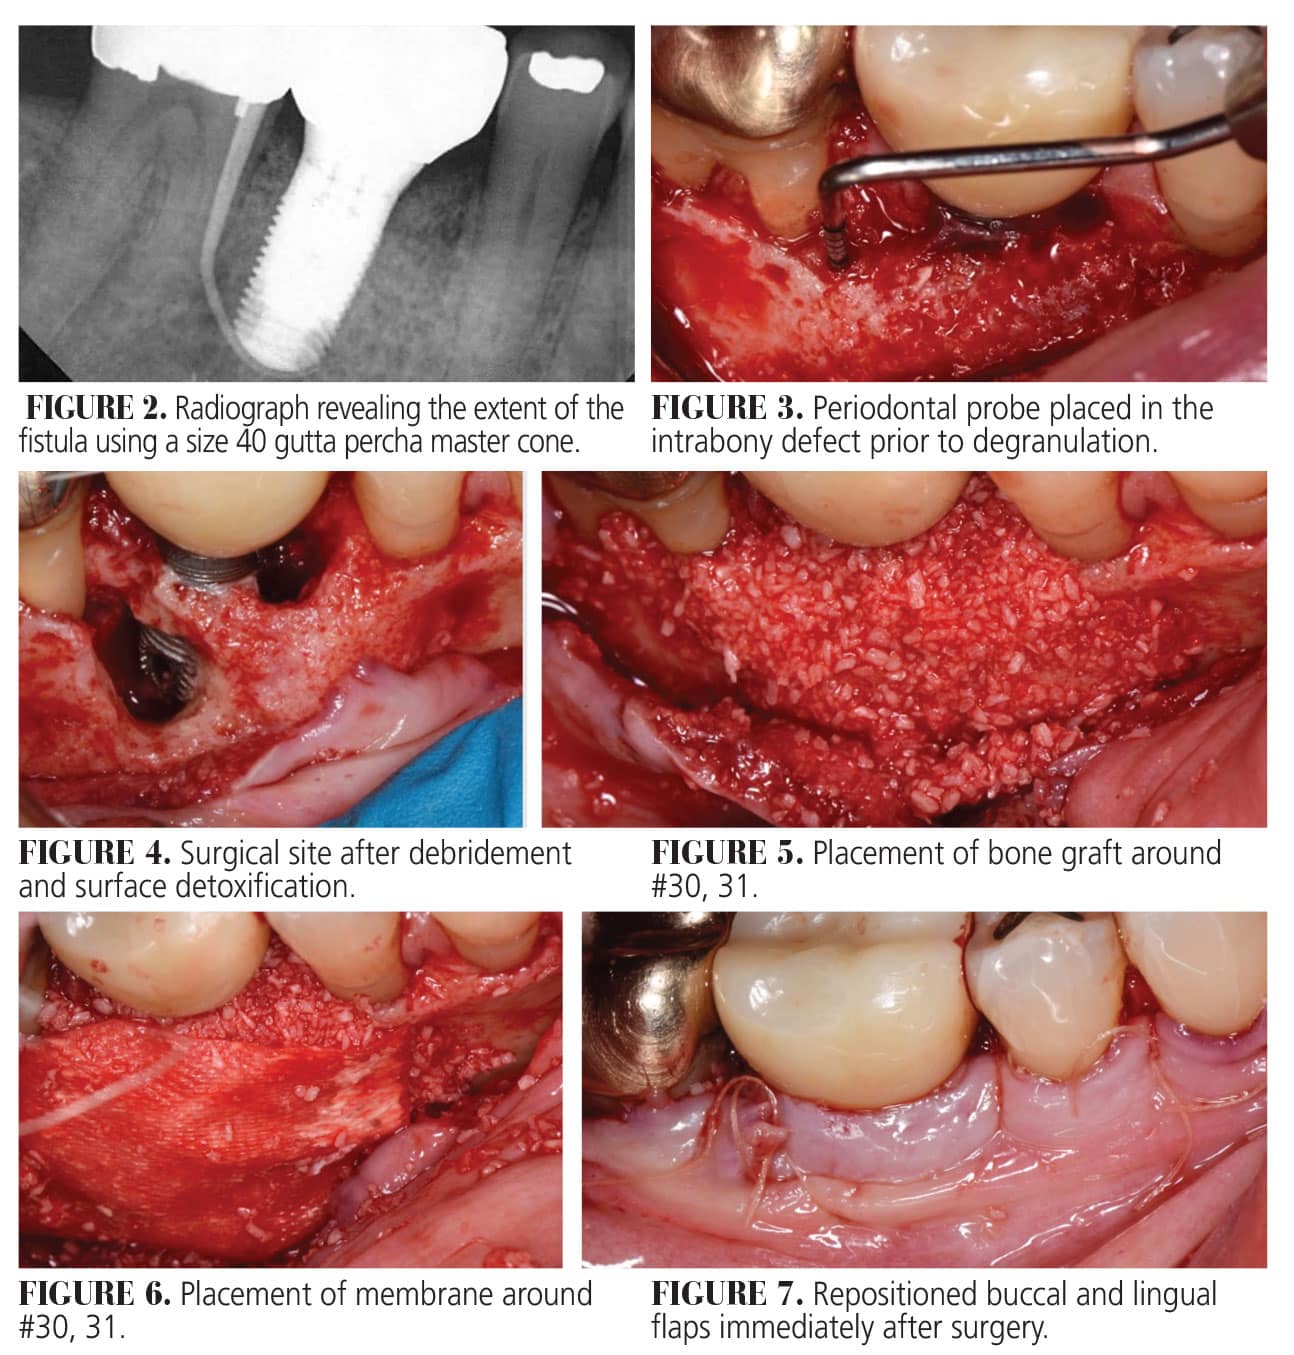

Active lesions require surgical intervention to prevent further osseous breakdown and to mitigate patient symptoms. This can include implant removal and replacement, implant flap debridement, or regenerative therapy using a bone graft, membrane, and/or growth factor. Some protocols also include resection of the implant apex for complete disinfection.8